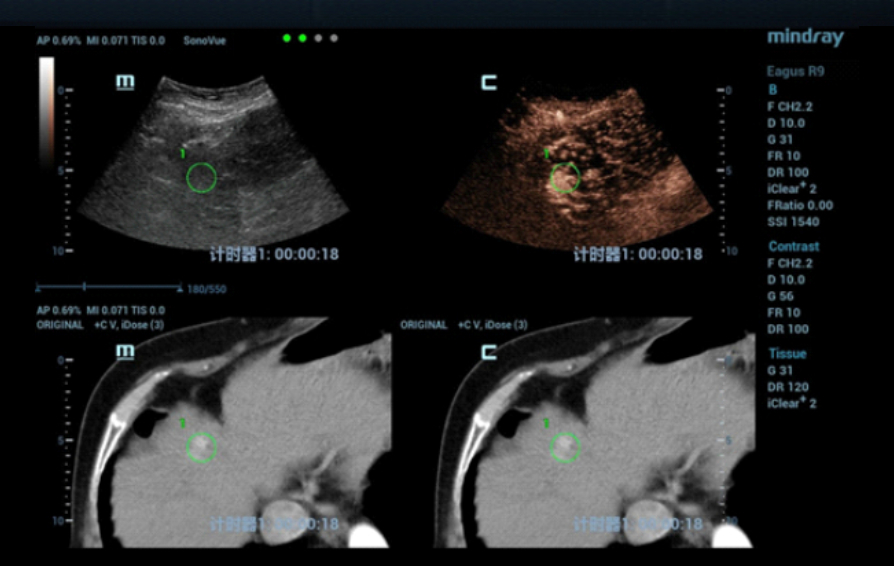

64? ???? 30? ??? ??B? ?? ??????, ???? S7?? ???? ??? ???? ?????? ?????. 3?? ?? MR? S4 ??? ?? ??? ?? ???? ???? ??? ??????. ???? Contrast-enhanced CT(??? ?? CT??)? ???? ?? S4 ??? 1.5???? ?? ???? ???? ??? ???????. ??? ??? ??? ???? ??? ??? ??? ??? ?????.

CT??? ??? S4?? ??? ??? ?? ???????? ??? ?????. CEUS(Contrast-Enhanced Ultra Sound)????? ?????? ??? ??? ??? ??? ???? ? ??? ???? ???? ??? ???????.

??? ??? ?? ????? ???(MWA)? ?? ?????? ?? ?????? ??? ???? ??? ?? Contrast-enhanced CT? ???? ??? ?? ??? ??? ?? ??? ?? ??? ????? ???? ???? ????? ??(MWA)? ??? ???????.

? ??? B? ??? ???? ??? ??? ??? ??? ??? ???? ?????? ?????. S4 ??? ?? ??? ?? ???? ?? MWA? ???? ???????.

??? ????? ??? 2D ??? ??? ???? ???? ???? ??? ? ????? ??? ??? ?? ?????? ???? ?? ??? ???? ???? ??? ? ?????. ??? ??? ???? ??? ?? CT ??? ??? ???? ??? ??? ??? ?? MWA? ?? ???? ??? ???? ?????. CEUS(Contrast-Enhanced Ultra Sound)? ???? ?? ? ??? ??? ????, ?? ? ?? ??? ???? ?? ?? ??? ???????.?